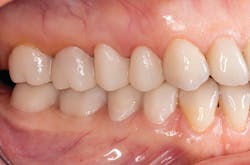

A patient presented with multiple deficient restorations, discolored teeth, and attrition (figures 1–4). The patient’s treatment plan was a full-mouth rehabilitation with a combination of veneers, crowns, and onlays.

Esthetic and functional prototypes are an effective way to evaluate esthetics and function of a proposed restorative plan, all while spreading the cost of definitive treatment over time. Esthetic, functional, and long-lasting restorations can be achieved if clinical and laboratory protocols are carefully followed using adhesive additive techniques.